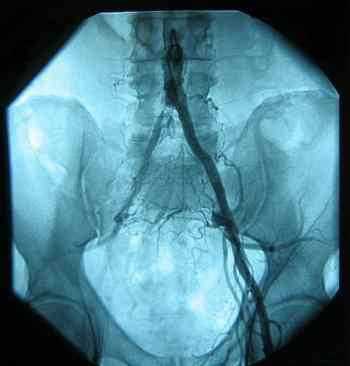

This sounds more like a condition known as intermittent claudication; it's angina in the leg, caused by a blockage of the artery in the groin area.